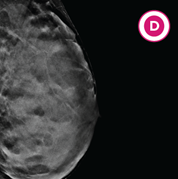

D. Extremely dense